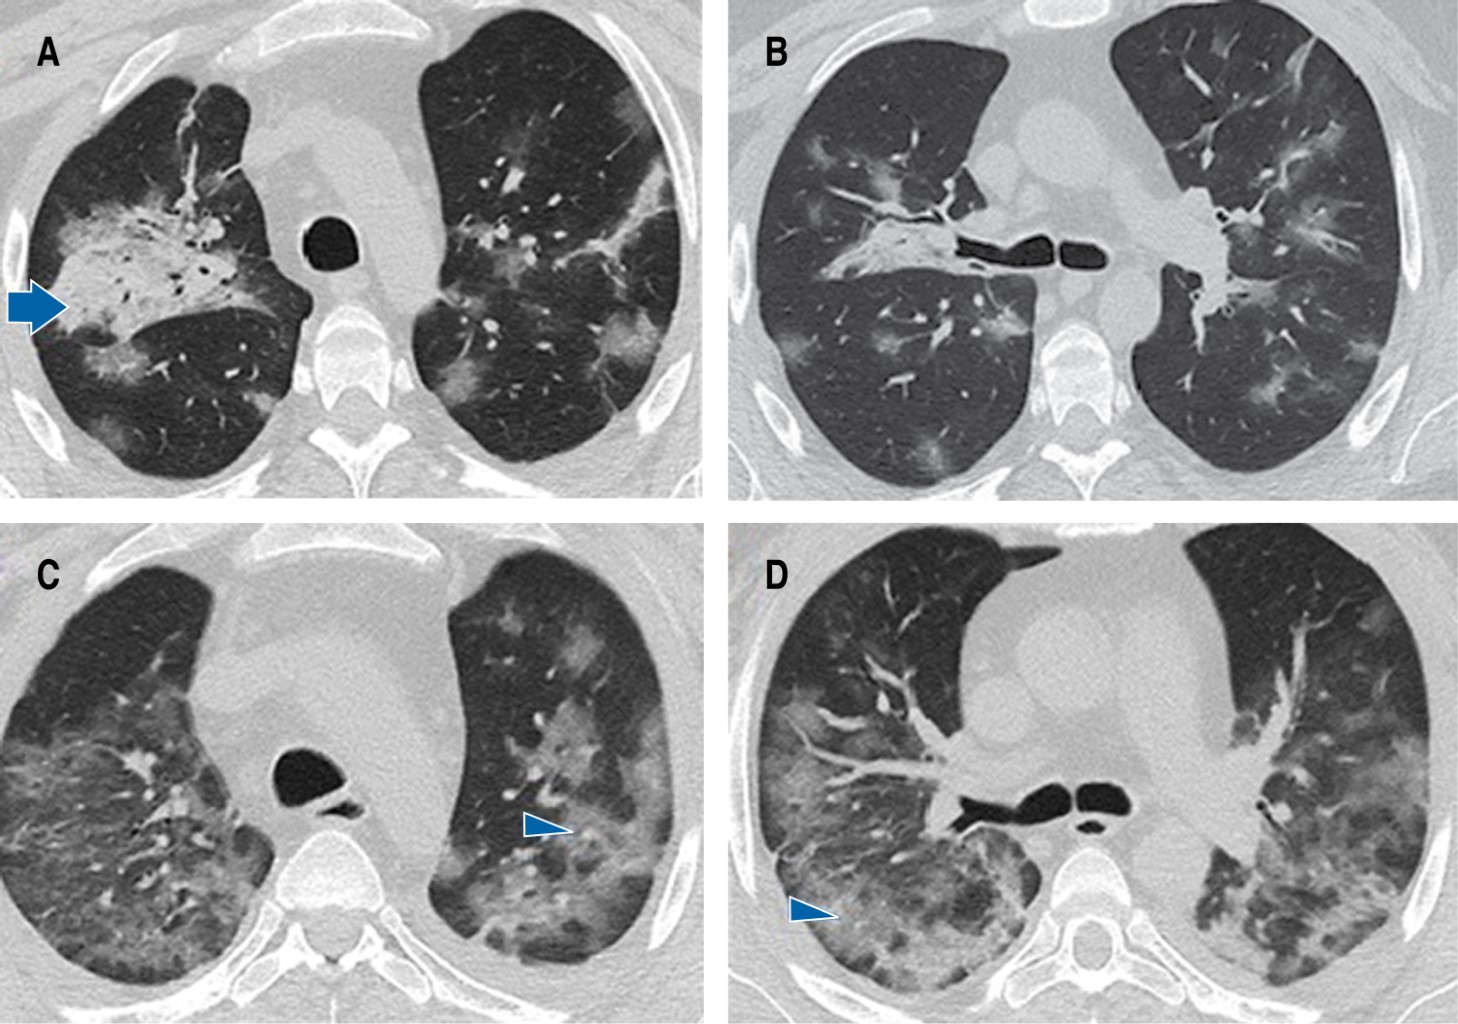

Paciente masculino de 36 años de edad con historia de trasplante renal de donador vivo relacionado (2003) por hipoplasia renal bilateral. Presentó rechazo humoral en noviembre de 2021 y requirió manejo inmunosupresor con rituximab, para posteriormente recibir micofenolato, prednisona y tacrolimus, condicionando toxicidad hematológica e inmunosupresión grave. Además sufre de hipertensión arterial sistémica secundaria, en tratamiento con calcioantagonista e inhibidor de la enzima convertidora de angiotensina II. Ingresó por cuadro clínico de cuatro días de evolución caracterizado por fiebre de 39 oC, disgeusia, anosmia, tos, mialgias, artralgias. Acompañándose de disnea progresiva hasta modified Medical Research Council (mMRC) 4 y saturación por oximetría de pulso (SpO2) de 88%. Al momento de su ingreso a urgencias presentaba presión arterial: 105/65 mmHg, frecuencia cardíaca: 85 lpm, frecuencia respiratoria: 29 rpm, temperatura: 36.7 oC, SpO2: 87%, gasometría arterial (GA) presión arterial de oxígeno (PaO2): 57.6 mmHg, presión arterial de dióxido de carbono (PaCO2):36.6 mmHg, pH: 7.43, índice de presión arterial de oxígeno/fracción inspirada de oxígeno (PaO2/FiO2): 274 mmHg. La tomografía simple de tórax confirmó la presencia de zonas en vidrio deslustrado de distribución aleatoria tanto periférica como central que afectaban más de 60% del parénquima pulmonar (Figuras 1A y 1B), además reveló pancitopenia. La prueba de reacción en cadena de la polimerasa retrotranscriptasa (PCR-RT) para SARS-CoV-2 en exudado nasofaríngeo fue positiva. Se inició tratamiento de soporte, dexametasona 6 mg cada 24 horas y anticoagulación profiláctica con enoxaparina. Sin embargo, a las 24 horas del ingreso hospitalario desarrolló síndrome de insuficiencia respiratoria aguda grave (PaO2/FiO2: 49.4 mmHg) y choque séptico. Se realizó una segunda tomografía de tórax simple que evidenció importante extensión de la neumonía (Figuras 1C, 1D y 2), de modo que ingresó a la unidad de cuidados intensivos (UCI) para manejo avanzado de la vía aérea y ventilación mecánica asistida. Debido al deterioro clínico y radiológico y al tratarse de un paciente con toxicidad hematológica por inmunosupresores, se efectuó lavado bronquioloalveolar en el que se identificó CMV mediante reacción en cadena de la polimerasa/ácido desoxirribonucleico cuantitativa (PCR/ADNc) para citomegalovirus: 554 copias/mL. El curso clínico del paciente fue tórpido, requirió de aminas vasoactivas y terapia sustitutiva de la función renal. Sin embargo, tras la administración de valganciclovir 900 mg cada 24 horas por 21 días, aunado al resto del tratamiento, la evolución fue favorable. Se realizó traqueostomía percutánea por debilidad muscular y ventilación mecánica prologada, se logró el retiro de ventilación mecánica tras 26 días de estancia en UCI, además recuperó función renal que permitió suspender la terapia sustitutiva de la función renal. El paciente egresó cinco días después del hospital con oxígeno suplementario 2 L/minuto y rehabilitación física y respiratoria. Se hizo prueba de deglución y revisión endoscópica de la vía aérea 10 días después del egreso, en la que se descartaron malacia y estenosis, se retiró la cánula de traqueostomía.